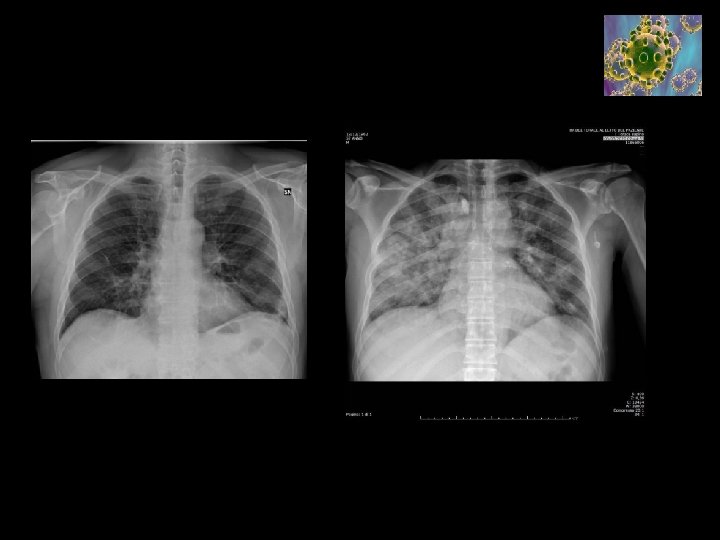

Clinical Course • • • Severe Acute Respiratory Infection (SARI) Type I respiratory failure (often hypocapnic) ARDS Near normal compliance lungs Severe shunt Secondary Complications – – Septic Shock Acute Renal Failure Myocarditis Glucose abnormalities and ketoacidosis • 7 -10 days IPPV required